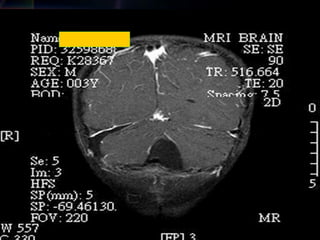

Post-operation

26

2013/12/7

33